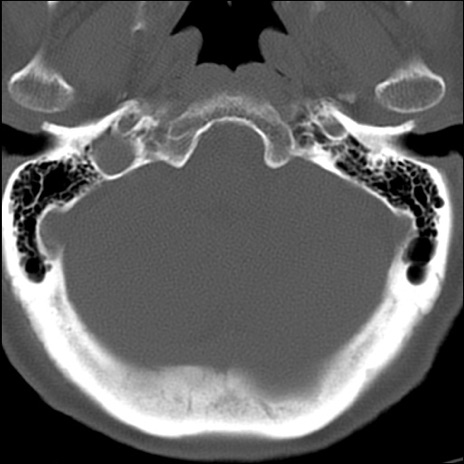

症例48 頚椎CT(横断像)

頚椎CT